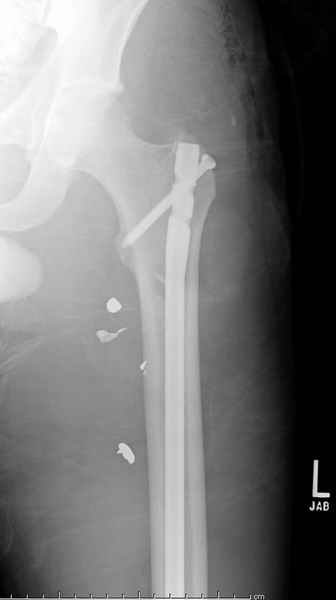

Учитывая, что больной получил травму не во время визита в церковь, и он является одним из представителем 40 миллионного “outstanding itizen”, без медицинской страховки, без работы в свои 39 лет, и без надлежающей ортопедической дисциплины у которого отсутсвует страх стрессового перелома, было рекомендовано оперативное лечение: профилактическое антеградное интрамедуллярное штифтование.

Методика штифтования при отсутствии большой зоны перелома как при онкологических профилактических штифтованиях, расверливание интрамедуллярного канала проводим с предварительным наложением дополнительного дренажного отверстия в дистальном отделе бедра (в данном случаи в канале оставили 6.5 мм канюлированный шуруп), иначе при создании давления в канале во время сверления имеется опасность эмболизации легочной артерии тромбом.